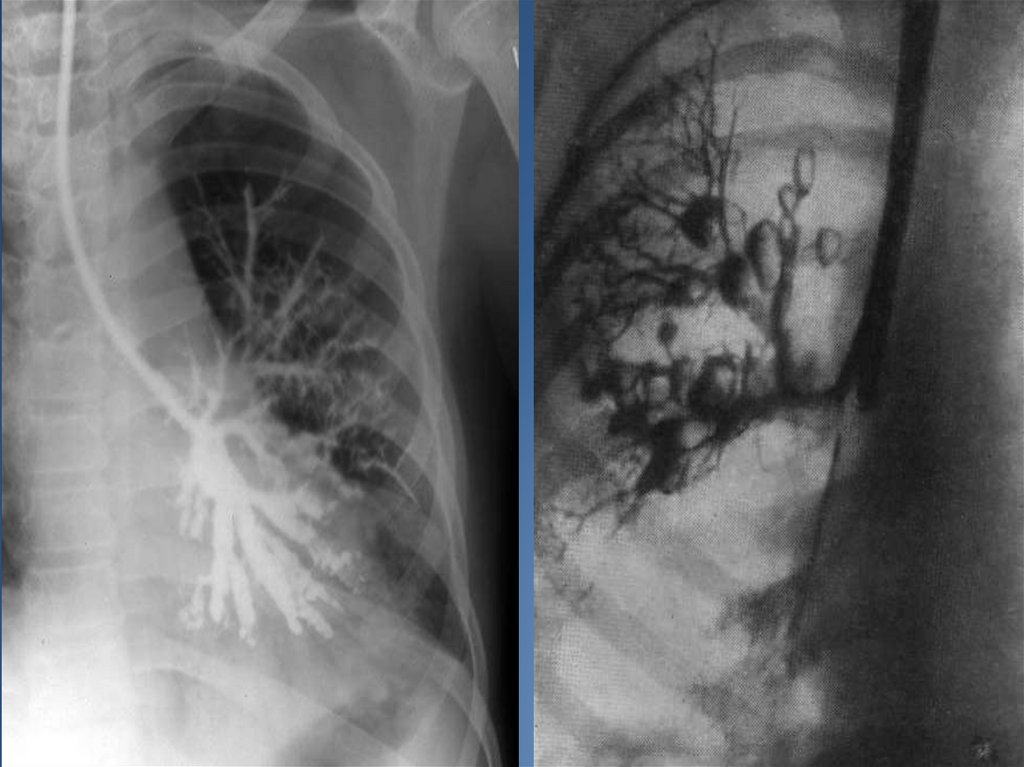

При стихании процесса проводят контрастную бронхографию для выявления характера и

локализации бронхоэктазов с целью последующего возможного оперативного их

удаления.

Диагностика: рентгенологический метод исследования (прямой и боковой);

исследование мокроты с нахождением в ней атипичных клеток, также

исследуется бронхиальный секрет и плевральный экссудат; компьютерная

томография; бронхоскопия (проводится забор пораженной ткани для

гистологического исследования; бронхография.